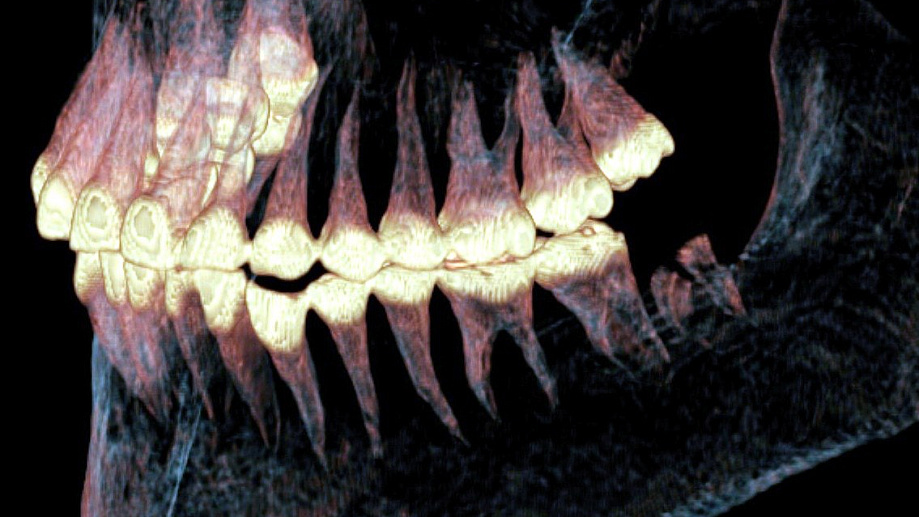

Experts at Novosibirsk State University (NSU), Russia, used a CT scan to examine her skull, hidden beneath layers of mummified tissue.

The scan showed she had suffered a severe head injury in life – her right jaw joint was destroyed, ligaments torn, and her lower jaw displaced beneath the skin.

The scan revealed two small holes deliberately drilled in the bone during her lifetime, each surrounded by a ring of new bone growth – clear evidence of healing.

Traces of elastic material, probably horsehair or tendon, were found inside the holes, suggesting they were used as a primitive surgical ligature to stabilise her jaw.

Further proof of the operation’s success came from her teeth – those on the injured side were intact, while teeth on the healthy side were worn from overuse, indicating long-term chewing and survival.